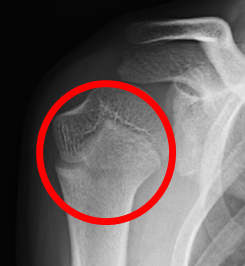

後方型野球肘の画像

肘の後方

正常

(レントゲン)

肘頭骨端線離開